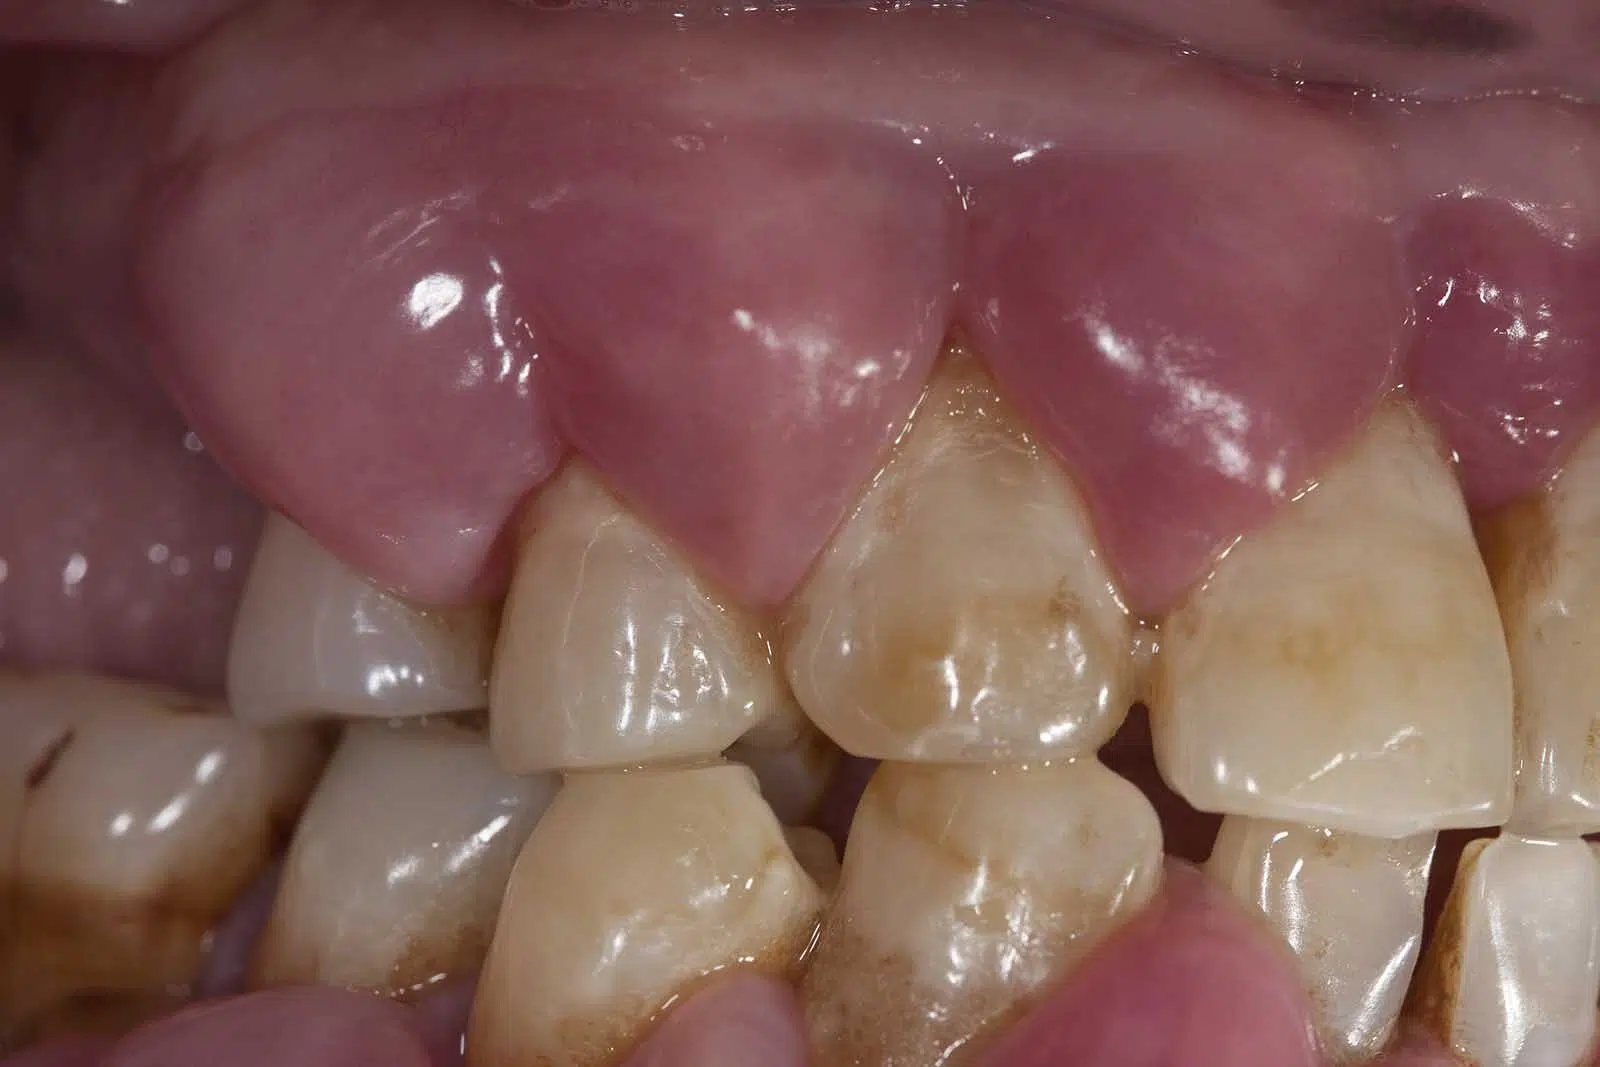

What Is An Endodontist Vs Periodontist . They still have the same skills as a dentist but have undergone additional specialized training. Endodontists and periodontists are dental specialists who focus on different aspects of oral health. Find out the difference between an endodontist and a periodontist, their qualifications, and when to seek specialized care. Like an endodontist, a periodontist is a dentist who has the same skills and credentials as a general dentist but has also gained education and certification in treating, diagnosing and managing periodontal disease, as the american academy of periodontology (aap) states. What is an endodontist vs. Endodontists and periodontists are both dental specialists, but they focus on different aspects of oral health. An endodontist is a dental specialist that treats your tooth’s root, pulp, and any related pain. Here are some signs that you should be referred to an endodontist: An endodontist specializes in issues with the inside of teeth, while a periodontist specializes in issues with the gums and supporting bone structure. An endodontist is a dentist who. Endodontists treat the pulp and roots of teeth, while.